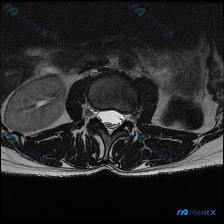

刚整理了一份很有警示意义的读片病例,分享给大家,这个坑平时读片真的很容易踩。 病例基本信息 临床诉求:患者因腰痛就诊,临床怀疑椎间盘病变,提供一张腰椎MRI T2加权轴位影像请读片。 影像基础评估 这是一张腰椎横断面(轴位)T2加权影像,清晰度和信噪比都不错,没有明显运动伪影,可以清楚辨认椎体、椎弓...

刚整理了一份腰椎MRI读片病例,只有单张轴位T2加权图像,把完整的分析思路整理出来和大家分享。 一、影像基本信息 这是一张腰椎MRI轴位T2加权图像,清晰度良好,解剖结构辨识度高: - 扫描水平为腰椎单个节段(大概率L4/5或L5/S1,具体需结合矢状位确认) - T2序列特征符合典型表现:脑脊液高...

整理了一份腰椎MRI读片讨论,给大家分享一下思路。 病例影像基础信息 本次仅提供放射影像-腰椎MRI-T2序列-轴位单张图像,扫描层面为腰椎某一节段,视觉判断符合腰4/5或腰5/骶1椎间盘水平,无临床病史、体征及其他检查资料,核心问题是明确该层面是否存在椎间盘病变相关影像学表现。 影像具体读片结果...